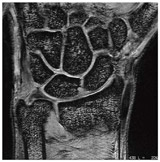

![]() 図7 右肩腱板部分断裂例 (8chショルダーアレイコイル) FSE T2WI(脂肪抑制画像), FOV 16cm,スライス厚 4mm, 2分57秒 |

●関節への臨床応用

谷本:関節領域では,1.5Tよりも3Tの方がはるかに高画質です。特に,肩と膝の画質はすばらしいです。

奥田:腱の損傷を検出する際には脂肪抑制T2強調画像を撮像していますが,1.5Tでは高信号な部分は明瞭に描出されるものの,TEをやや短くしないと,背景の信号が弱く,解剖がよく見えないという状況でした。しかし3Tでは,TEを長くしたままでも背景の解剖のコントラストがある程度残るので,病変部位の同定が容易になりました。これは,S/Nの向上によるところが非常に大きいと思います。

谷本:3Tでは,前立腺やその他の領域もきわめて高画質が得られるようになりましたが,関節が最も1.5Tとの差が大きいかもしれません。

奥田:軟部腫瘍なども,LAVA-FLEXを使えば非常に均一に脂肪が抑制され,高画質が得られます。

谷本:最近では,SE法のT1強調画像は撮像しなくなりました。LAVA-FLEXのin-phaseで代用していますが,それでもまったく問題はありません。